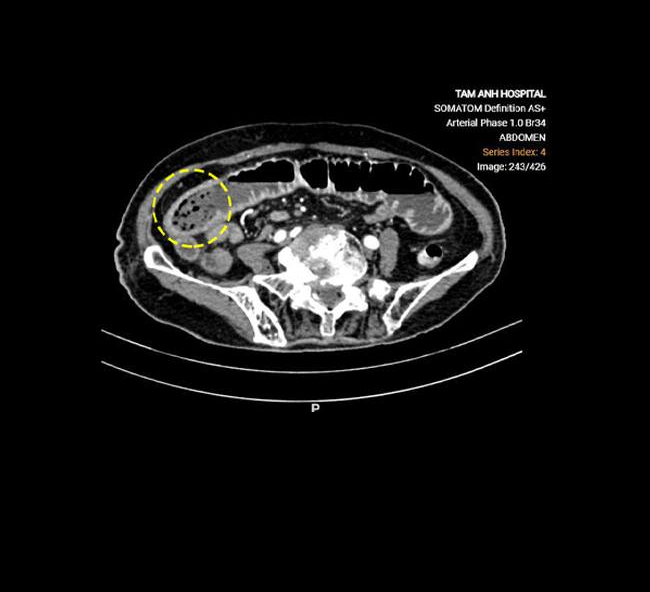

ThS.BSCKII Lê Văn Lượng, Khoa Ngoại tổng hợp, cho biết phim chụp X-quang ổ bụng của cụ Sinh phát hiện mức nước-hơi (tình trạng dịch và khí bị ứ trệ trên các quai ruột tắc giãn tạo ra các hình ảnh trên phim X-quang chụp bụng với mức nước phía dưới và hình hơi hình vòm phía trên). Phim chụp CT thấy khối bã thức ăn làm đoạn giữa ruột non giãn nghiêm trọng 4,4 cm, gây tắc ruột cơ học.

Khối bã thức ăn của cụ Sinh trên phim chụp CT - Ảnh BVCC